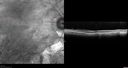

82 year old man with a sister with RP and no other family members. He has trouble with night vision. VA 20/25 OD, 20/32 OS. Note the symmetry in the FAF images typical for a dystrophy. The photos show bone spicules, arteriol attenuation and optic nerve pallor

Retinitis Pigmentosa - Autosomal Recessive - 82 year old man with Good Vision484 viewsVA 20/25, 20/32 - Bone spicules in periphery - FAF is very symmetric     (0 votes)